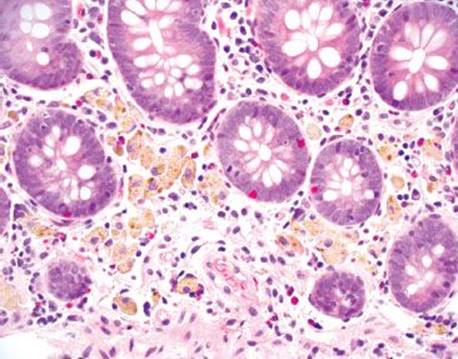

Melanosis coli refers to coarse, brown-black pigment in the cytoplasm of the colon’s resident macrophages. Despite the name, ultrastructural studies demonstrated the pigment is lipofuscin, not melanin (this particular factoid is a favorite among those who write test questions!).111 The pigment is derived from stimulant laxatives containing senna, aloe-emodin, chrysophanol, cascara, frangula, and rhein.112 The purgative effects of such preparations stem from their ability to increase colonic motility and decrease colonic absorption, resulting in decreased transit time and softer stools. The endoscopic images in patients with melanosis coli can be impressive (Fig. 4.231). Any region of the colon can be affected with no consistent regional pattern of involvement: some claim the distal colon is most affected, while others found the changes most pronounced proximally.113,114 Melanosis coli is seen in up to 73% of patients with chronic laxative usage and in up to 6% of biopsy and autopsy cases.115,116 Such findings have been documented within 4 months of regular laxative usage and the findings reverse 6 to 11 months following cessation (Figs. 4.232–4.238).117,118 Early literature suggested anthracoid laxatives were a risk factor for colonic neoplasia based on provocative animal and human studies showing an increased association of melanosis coli in patients with adenomas and carcinomas.119,120 Today, this theory has been abandoned.121,122

Figure 4.233 Melanosis coli. Under oil immersion, note the bland cytologic features of the macrophages with perfectly round nuclei, delicate nucleoli, and abundant cytoplasm. The background shows scattered neutrophils secondary to an unrelated self-limited infection.